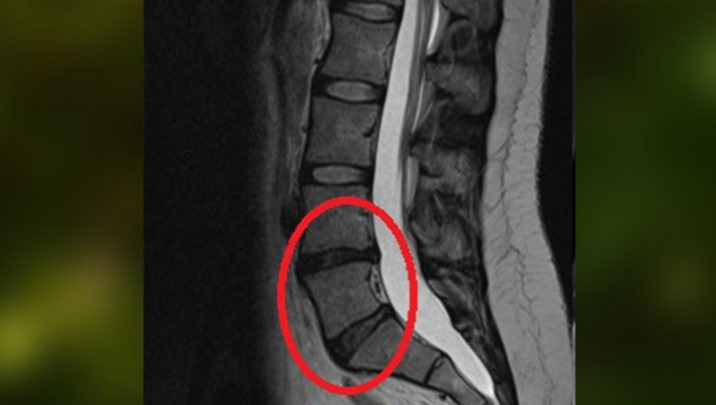

We finally found out what was wrong when Simone had an MRI in early 2022. The imaging showed that she has disc degeneration, disc protrusion and olisthesis (vertebrae slippage). In fact, the imaging clearly shows that two discs are black (see spine photo below inside the red oval) when they should be grey, meaning these discs are diseased. No wonder she’s in constant pain!